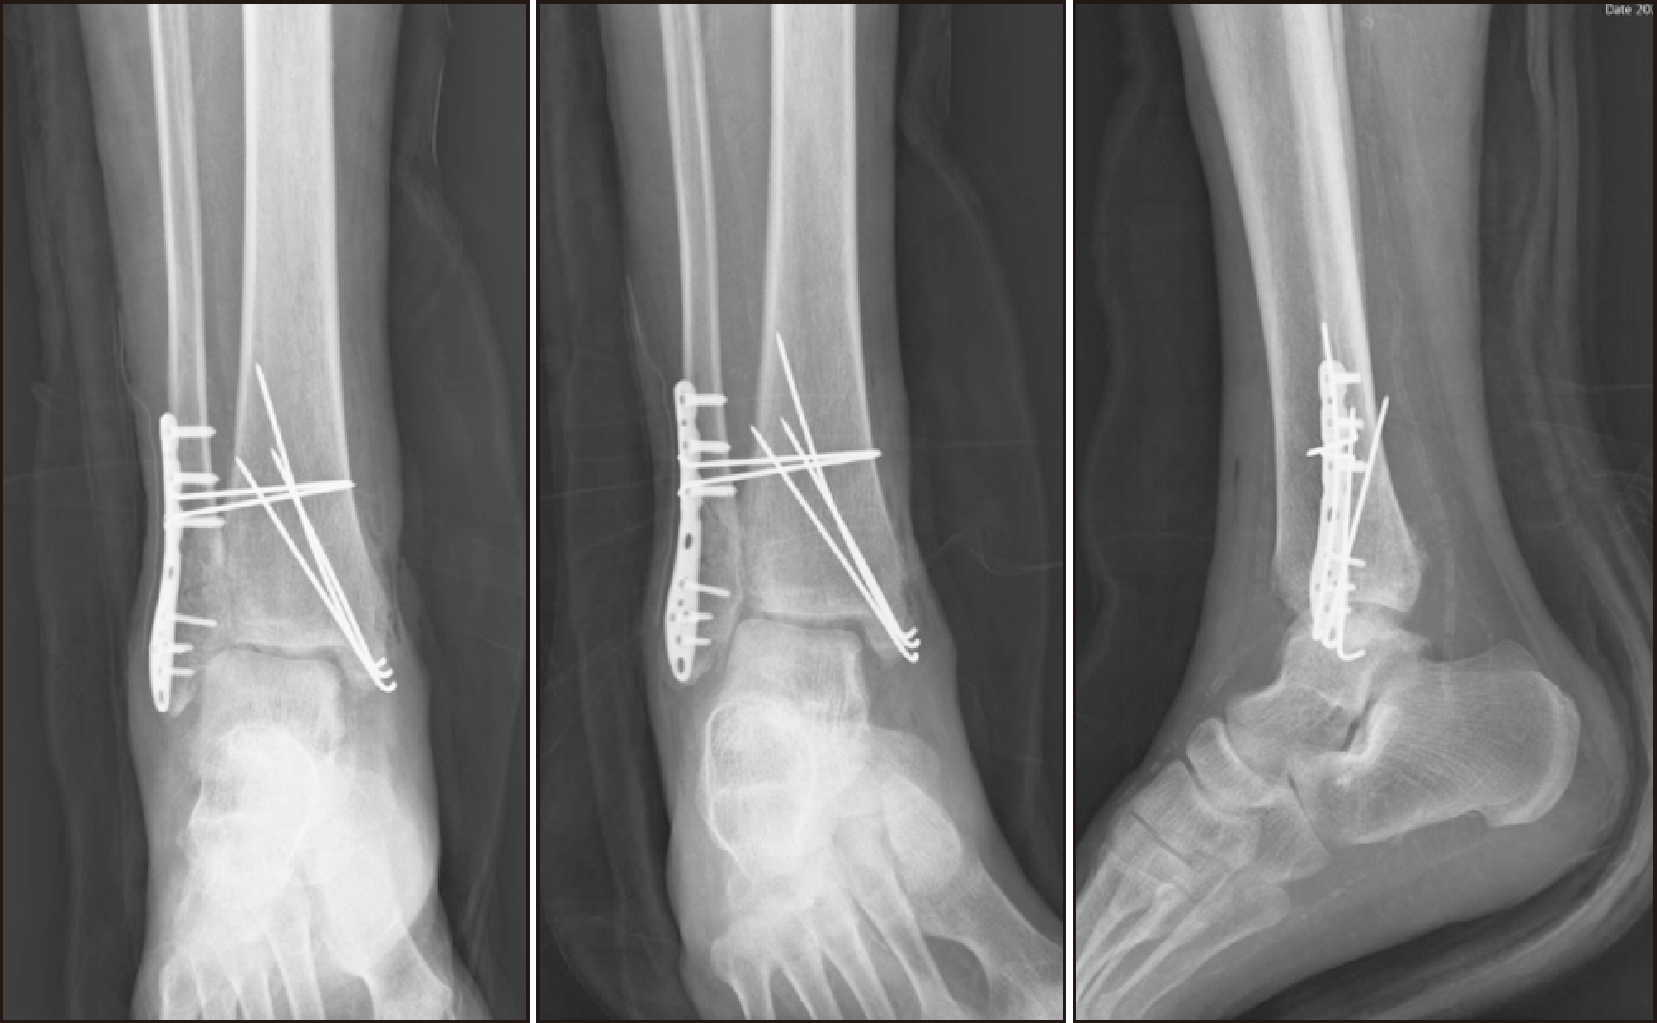

Six months post-operation, the patient presented with a plantar lesion emitting a foul odor, accompanied by a fever (39°C) and highly elevated CRP levels at 369.9 mg/L. At 3 months post-TTC fusion surgery, loosening of the fixed portion of the nail and loss of reduction were observed (Fig. 9). Imaging studies revealed a soft tissue defect at the sole, extending posteriorly to form a sinus tract or abscess (Fig. 10, 11). The patient underwent incision and drainage, along with removal of a loosened screw.

Figure 10

Clinical picture of soft tissue defect at the sole at 6 months post-tibiotalocalcaneal fusion.

Figure 11

(A) Radiograph at 3 months post-TTC fusion. (B) CT scan at 6 months post-TTC fusion showing soft tissue defect at the sole, extending posteriorly to form a sinus tract or abscess. TTC: tibiotalocalcaneal.

Figure 12

Findings at 8 months post-tibiotalocalcaneal fusion showing fever and operation site infection, accompanied by concurrent metal failure.